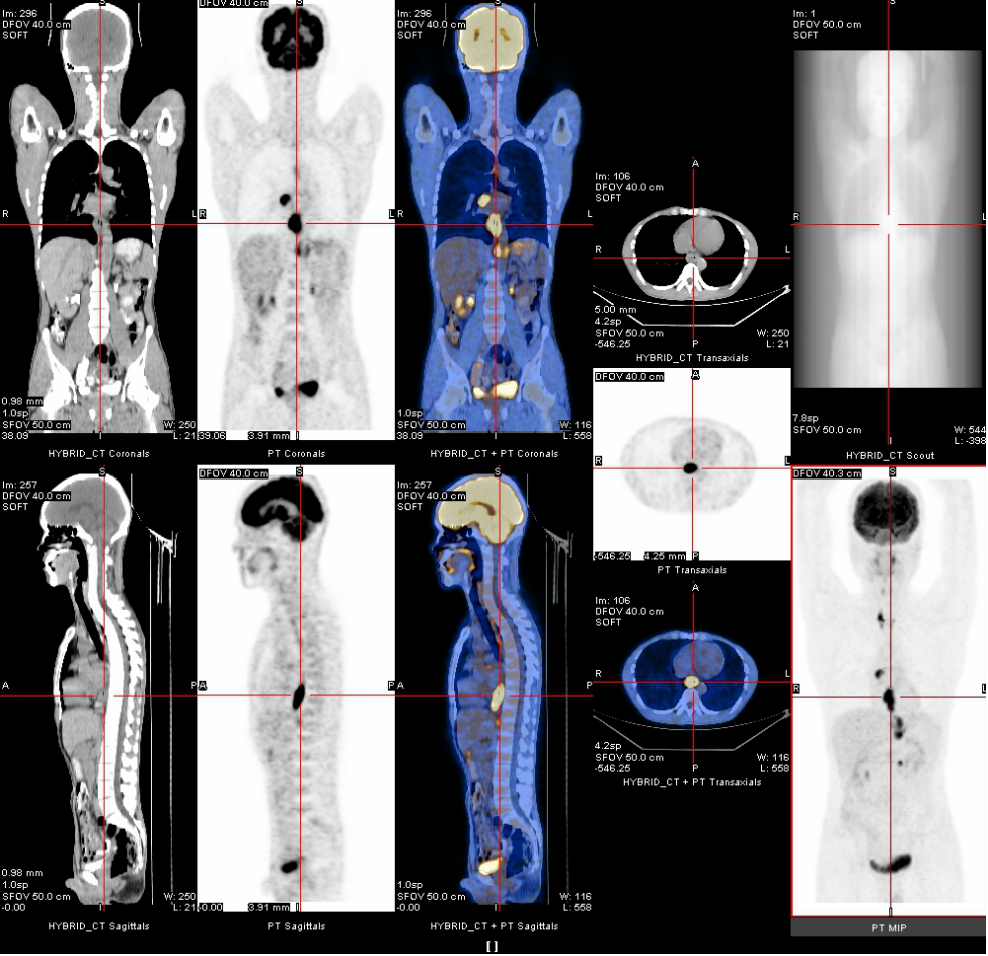

2020年3月13日

全身PET-CT示:1、食管胸中下段管壁不规则增厚,代谢增高,考虑食管癌。2、上纵隔胸廓入口区气管两旁、右下肺静脉后方、贲门区、肝胃间隙、降主动脉后方、膈肌脚后方、腹膜后腹主动脉左旁(左肾门下方平面)见多发高代谢肿大淋巴结,考虑淋巴结转移,建议随访复查。3、右肺上叶前段胸膜下小结节影,代谢未见增高,建议随访复查。4、右肺下叶外基底段条索影,考虑慢性炎性改变。5、双侧上颌窦轻度慢性炎症。6、双侧颈部多发小结节影,代谢未见增高,考虑淋巴结慢性炎性增生。7、肝左叶内侧段小钙化灶。